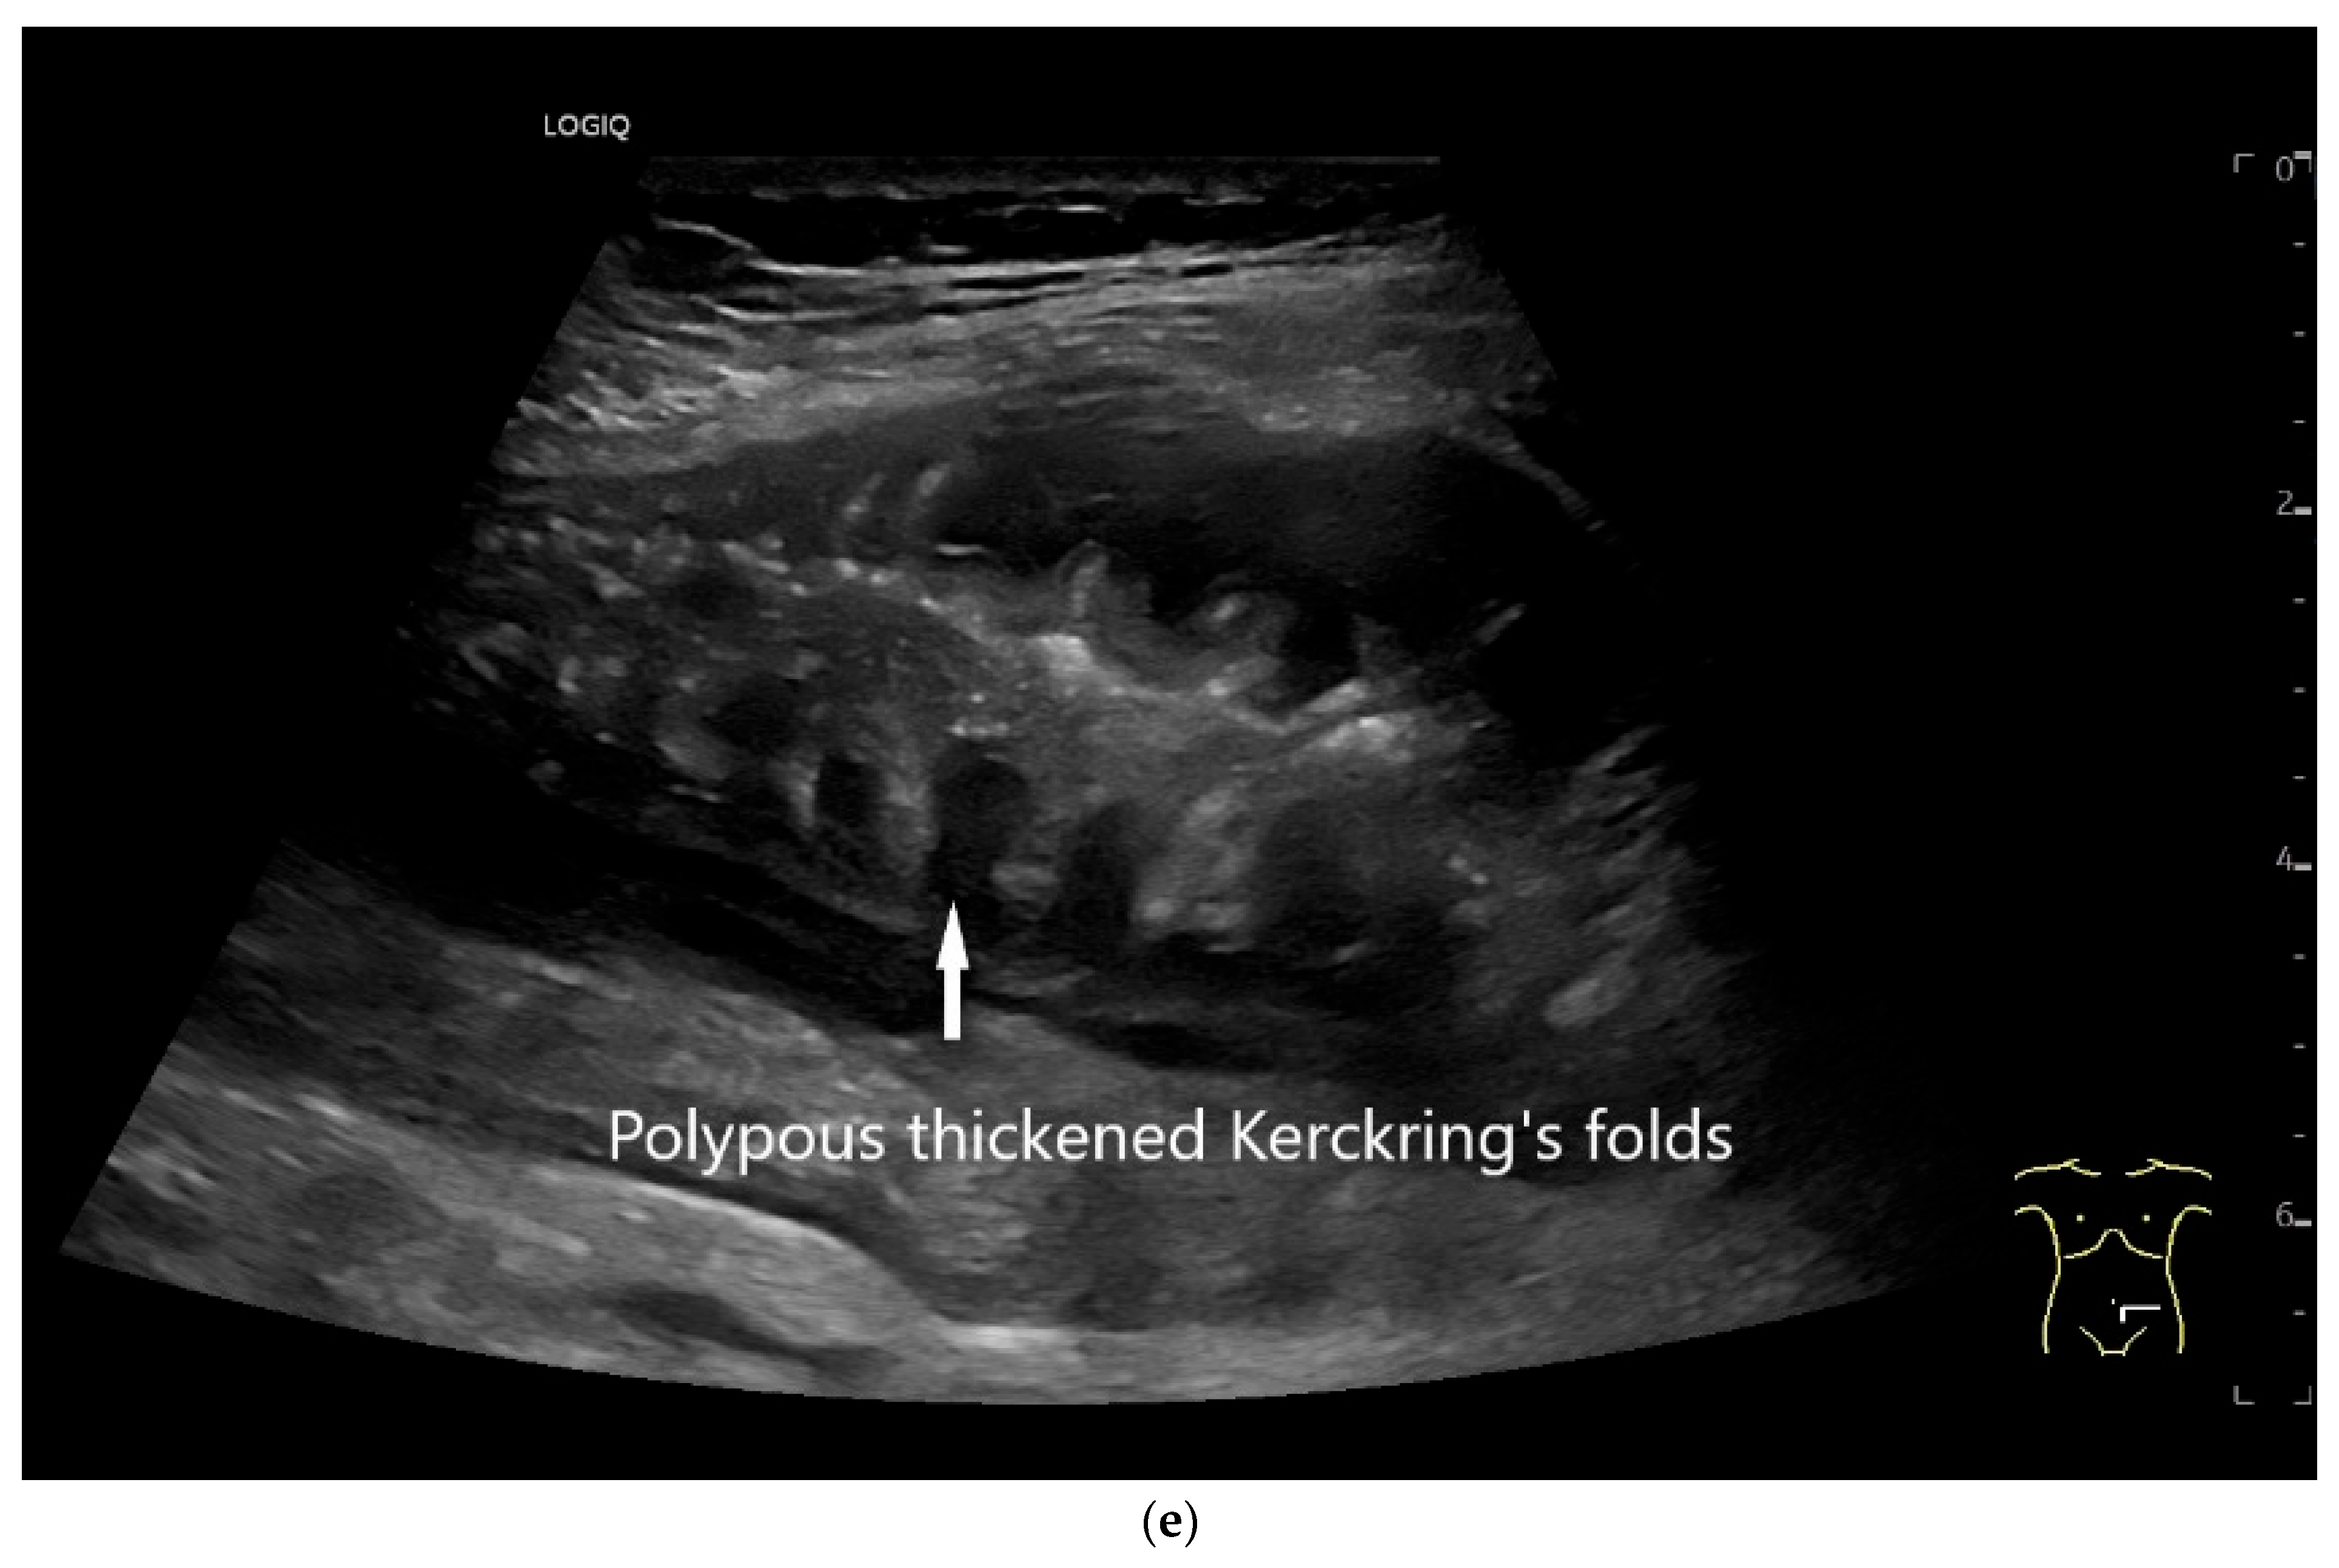

Ultrasound Imaging of Small Intestine NEN

| Neuroendocrine tumor | Small, nodular hypoechoic wall thickenings, mostly in the submucosa with spreading into the other layers. Usually with small vessels on CDI. Regionally enlarged lymph nodes. Multilocular manifestations are possible. |

| Lymphoma | Very pronounced wall thickening with marked hypoechogenicity. Large regional and distant lymph nodes. Look for splenic infiltration. Tumor vessels on CDI and hyperenhancement on CEUS. Heterogeneous hyperechogenicity of the mesentery with walling of the mesenteric vessels. Multiple localizations are possible. |

| GIST | Round hypoechoic masses, homogeneous or heterogeneous depending on size. They usually originate from the muscularis propria, which can be difficult to distinguish in US. Small vessels on CDI, hyperenhancement on CEUS. They move with the small intestine and can change position. |